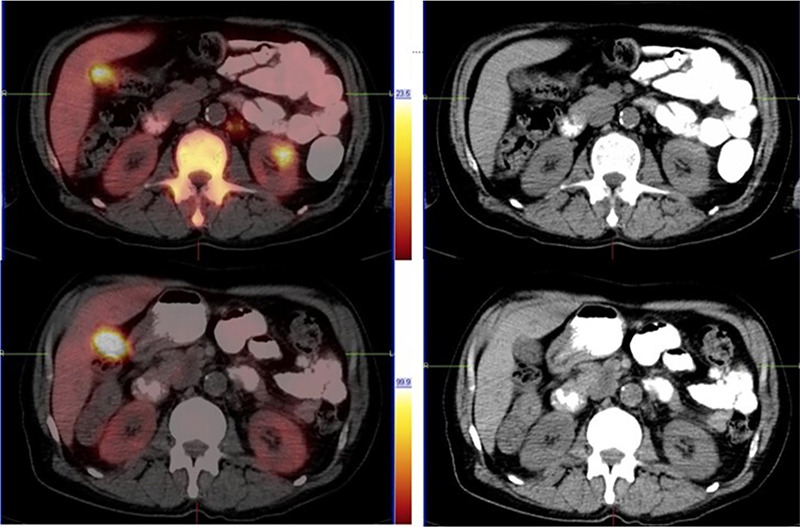

Prostate cancer typically follows a characteristic pattern of metastatic spread to the pelvic lymph nodes and bone. Atypical patterns of metastasis are rare but have been documented. In African men, this disease tends to follow a more aggressive course, with the possibility of an atypical site of metastatic spread. We present a case of a 58-year- old African male with metastatic castrate-resistant prostate cancer who presented with both typical and atypical patterns of metastatic disease detected by a fluorine 18 prostate-specific membrane antigen positron emission tomography/computed tomography scan. This patient also had a good response to radioligand therapy.